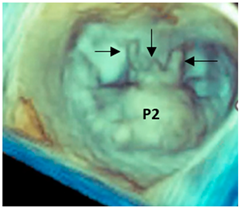

| Fibroelastic deficiency plus | This phenotype is characterized by a single scallop prolapse, but the involved scallop is redundant and affected by myxomatous degeneration. The remaining scallops are normal. Qualitative histological lesions in the prolapsed tissue of FED plus are similar to those of Barlow’s disease. It has been suggested that FED plus may be considered a sort of worsening stage of FED, leading to the hypothesis that the myxomatous changes could also be secondary to jet lesions. The figure shows a large P2 prolapse with ruptured chordae tendineae (arrows). |  |